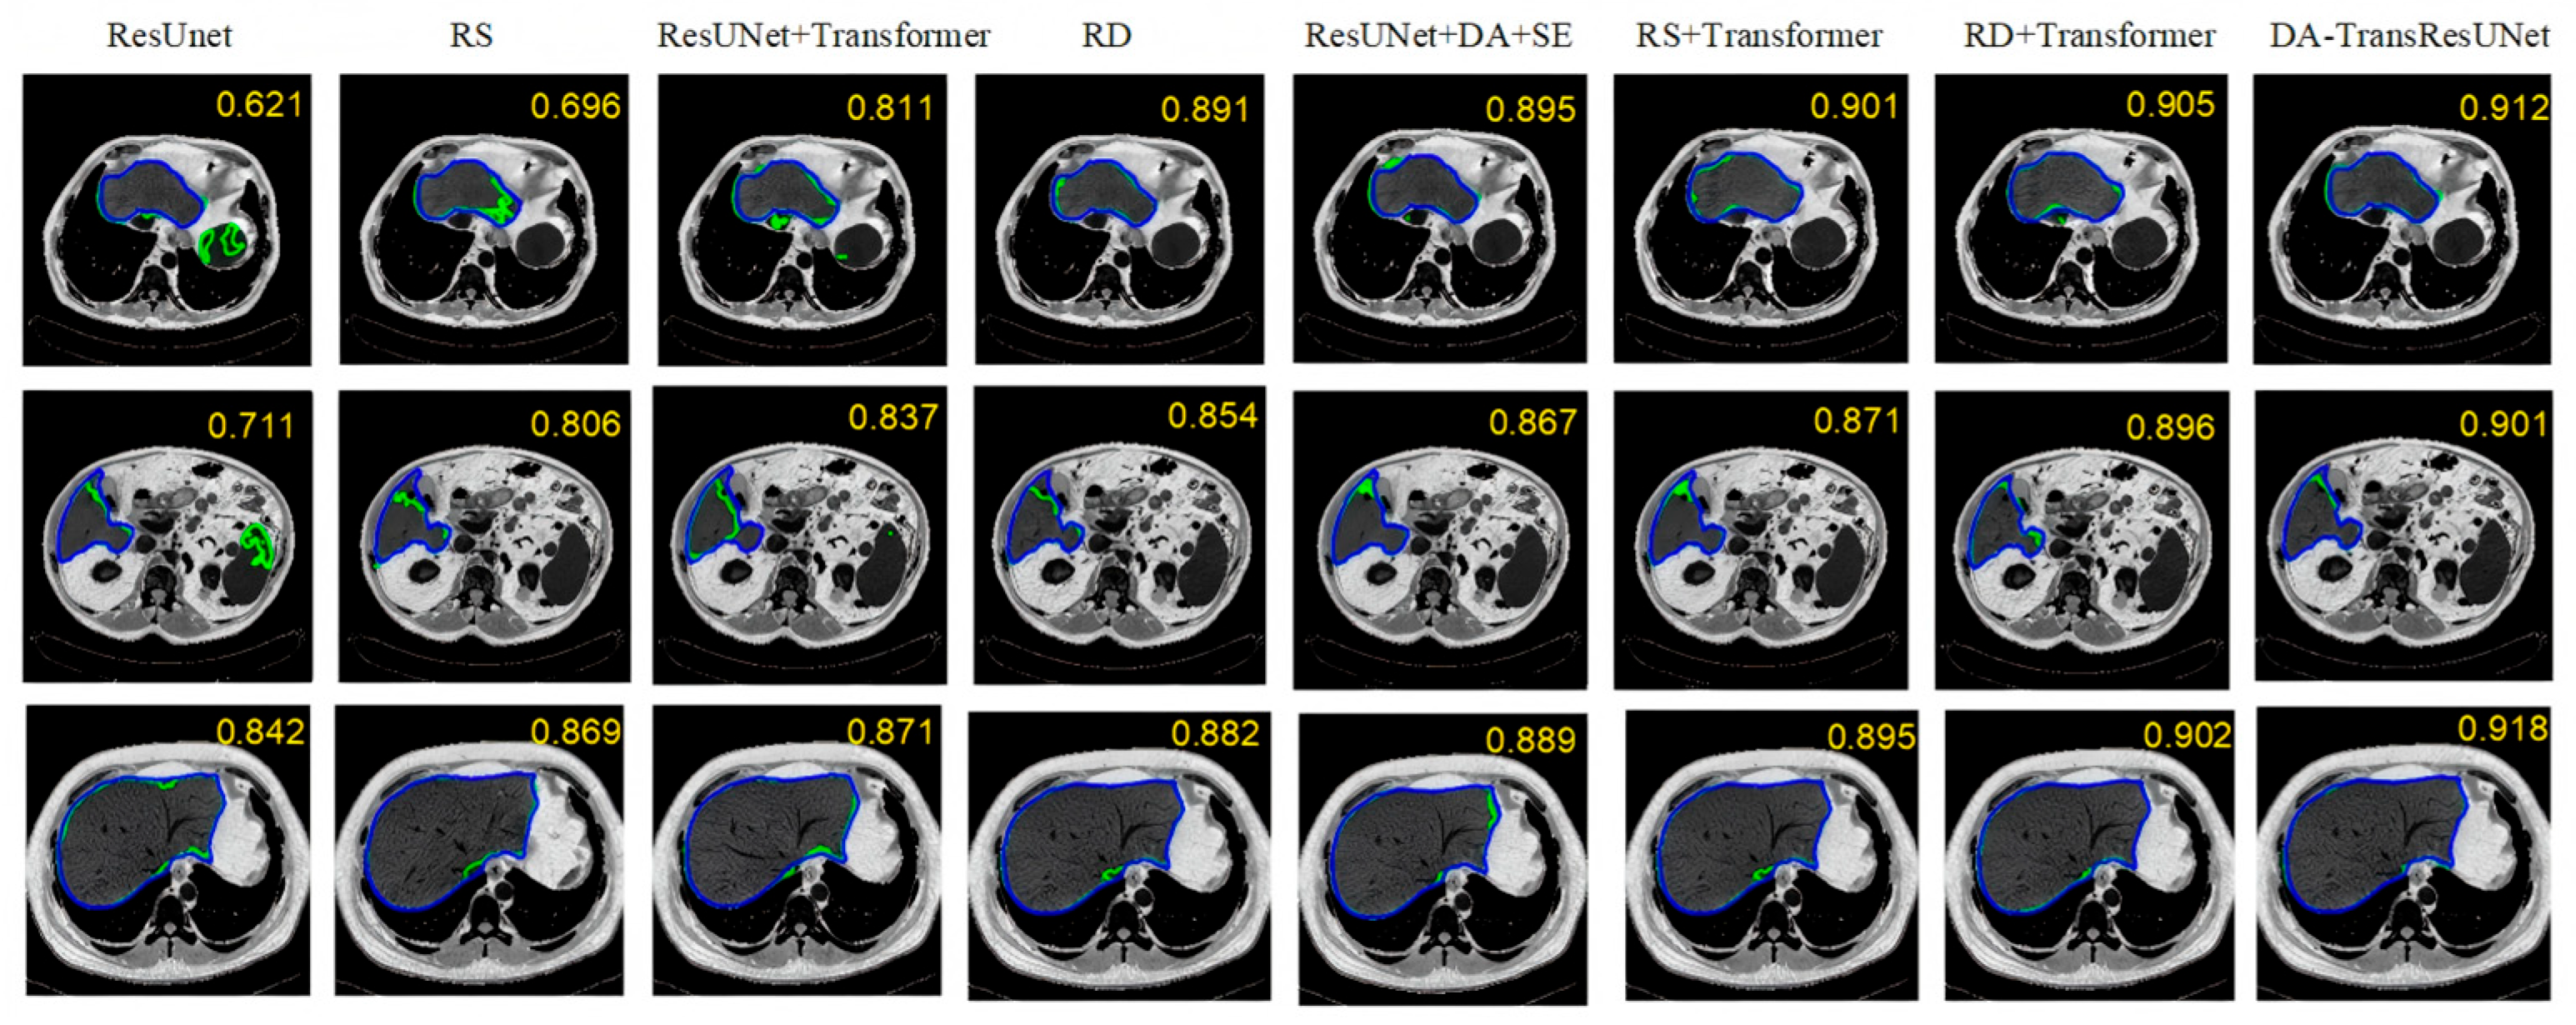

5.2. Comparative Experiment

| Model | DICE (%) | VOE (%) | RVD (%) | ASD (mm) | MSD (mm) |

|---|---|---|---|---|---|

| UKAN | 94.63 | 9.81 | −2.30 | 8.26 | 53.15 |

| KM-UNet | 94.88 | 9.22 | −1.95 | 8.20 | 51.97 |

| FCN | 91.83 | 14.64 | −6.91 | 9.03 | 58.59 |

| U-Net | 92.67 | 13.20 | −5.41 | 8.30 | 55.81 |

| Attention U-Net | 94.12 | 10.93 | −3.58 | 8.21 | 54.47 |

| RMAU-Net [18] | 95.21 | 8.19 | −0.40 | - | - |

| GCHA-Net [19] | 92.68 | 11.85 | −1.50 | - | - |

| SAR-U-Net | 94.98 | 9.42 | −2.15 | 8.08 | 52.61 |

| DA-TransResUNet | 95.22 | 7.52 | −1.02 | 7.97 | 37.58 |

| UKAN | 89.18 | 18.31 | −3.19 | 9.90 | 145.13 |

| KM-UNet | 90.05 | 17.44 | −2.11 | 9.06 | 135.47 |

| FCN | 78.57 | 35.29 | −12.36 | 15.54 | 174.04 |

| U-Net | 82.69 | 27.66 | −8.93 | 12.51 | 167.20 |

| Attention U-Net | 88.81 | 20.12 | −4.09 | 10.04 | 147.75 |

| SAR-U-Net | 90.51 | 17.11 | −1.51 | 8.98 | 129.14 |

| DA-ResTransUNet | 91.79 | 15.17 | 1.10 | 8.45 | 98.51 |